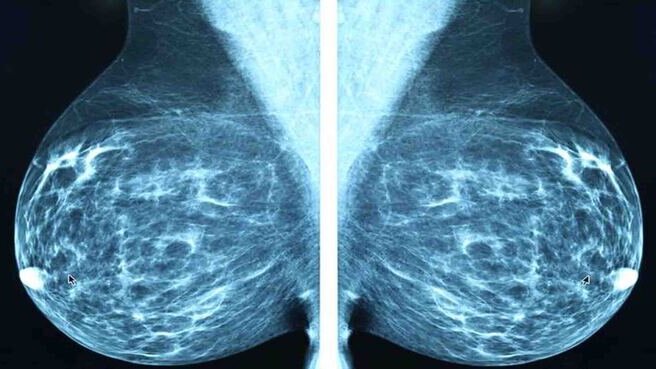

Vôi hóa tuyến vú là tình trạng lắng đọng canxi tại tuyến vú, thường gặp ở phụ nữ cao tuổi. Khó phát hiện tình trạng này thông qua quan sát bằng mắt thường hoặc cầm nắm, chỉ được phát hiện trên kết quả phim chụp X-quang. Vậy vôi hóa tuyến vú nguyên nhân là do đâu? Biện pháp phòng ngừa ra sao? Mời bạn đọc tìm hiểu thông qua bài viết dưới đây.

Vôi hóa tuyến vú là hiện tượng canxi lắng đọng và tích tụ bên trong mô vú tạo thành các hạt hay nốt canxi. Đa số các tình trạng vôi hóa tuyến vú đều không có dấu hiệu hay triệu chứng bất thường. Tình trạng này không gây đau, khó phát hiện bằng mắt thường và rất nhỏ để sờ thấy bằng tay. Hầu hết các trường hợp chỉ được phát hiện khi chụp nhũ ảnh hay còn gọi là X-quang tuyến vú.

Trên kết quả phim chụp X-quang tuyến vú, nốt vôi hoá được chia thành 2 loại như sau: